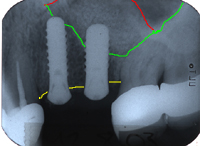

Abb. 6 zeigt den Verlust eines unteren Milchzahnes bei einem 26 Jahre jungen Patienten. Gesunde Nachbarzähne veranlassen uns, ein Implantat vorzuschlagen und auf eine Brücke zu verzichten, welche das Beschleifen der Nachbarzähne nötig gemacht hätte. Stark erschwerend ist allerdings, dass im Röntgenbild von Abb. 6 ein grosser Knochenkrater sichtbar ist.

Abb. 7 zeigt, wie das Knochentransplantat aus dem Kinn fixiert wird, um den Knochenkrater zu füllen. Nach viermonatiger Einheilung (Abb. 8) setzen wir das Implantat.

| Ursprünglicher Verlauf des Kieferkammes | |

| Neuer Verlauf des Kieferkammes | |

| Gebiet zwischen gelber und grüner Linie: Knochenaufbau | |

Im Röntgenbild von Abb. 9 sieht man, dass dreieinhalb Jahre später absolut perfekte Knochenverhältnisse ums Implantat herrschen. Abb. 10 zeigt die klinische Situation dreieinhalb Jahre nach dem Zementieren der Implantatkrone.